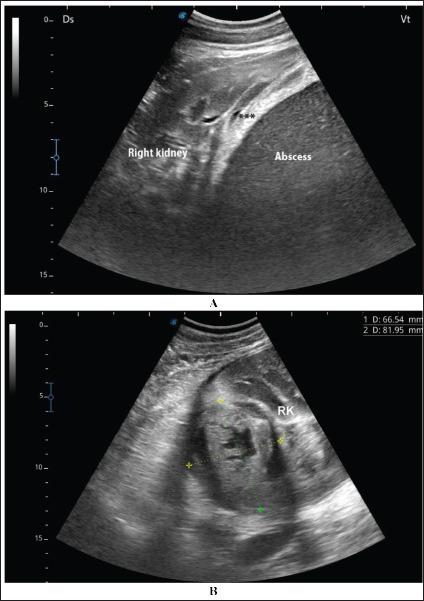

The signs of diseased camels included general gradual and/or progressive weakness, inappetence or anorexia, passage of dry feces, dysuria, bloody feces, lameness, bloody urine, and abdominal pain. Neutrophilic leukocytosis is the most significant hematological abnormality. Significant biochemical alterations included hyperproteinemia, azotemia, hyperglycemia, and increased serum alkaline phosphatase activity. Single or multiple renal abscesses were visualized sonographically compressing the renal parenchyma. Three abscesses measuring 5.2-15.0 cm were scanned in 2 camels; one affected the left and the other affected the right kidneys. In addition, two abscesses were imaged in 2 camels; both are affecting the left kidney. However, single abscesses measuring 3.6-14.0 cm in length were recorded in the remaining 13 camels; nine in the right and four in the left kidneys. The contents of the abscesses were hyperechogenic in 8 cases, hypoechoic in 4, isoechoic with hyperechoic foci in 3 cases, and heterogenous in 2. In 4 of the 17 diseased camels, hyperechoic urine and echogenic deposits were found within the urinary bladder. Bacteriological examination showed pure growth of in 10 coagulase-negative isolates, in 5 coagulase-positive isolates, and 2 unidentified species.

患病骆驼的体征包括全身逐渐和/或进行性虚弱、食欲不振或厌食、排干粪、排尿困难、血便、跛行、血尿和腹痛。中性粒细胞增多是最显著的血液学异常。显著的生化改变包括高蛋白血症、氮质血症、高血糖和血清碱性磷酸酶活性增加。超声检查可见单个或多个肾脓肿压迫肾实质。在2只骆驼中扫描到3个大小为5.2 - 15.0cm的脓肿;1个影响左肾,另1个影响右肾。此外,在2只骆驼中成像了2个脓肿;均影响左肾。然而,在其余13只骆驼中记录到单个长度为3.6 - 14.0cm的脓肿;9个在右肾,4个在左肾。脓肿内容物在8例中为高回声,4例为低回声,3例为等回声伴高回声灶,2例为不均匀回声。在17只患病骆驼中的4只,膀胱内发现高回声尿液和回声沉积物。细菌学检查显示10株凝固酶阴性分离株中纯培养物为[具体细菌名称未给出],5株凝固酶阳性分离株中为[具体细菌名称未给出],2株未鉴定的[细菌种类未给出]。